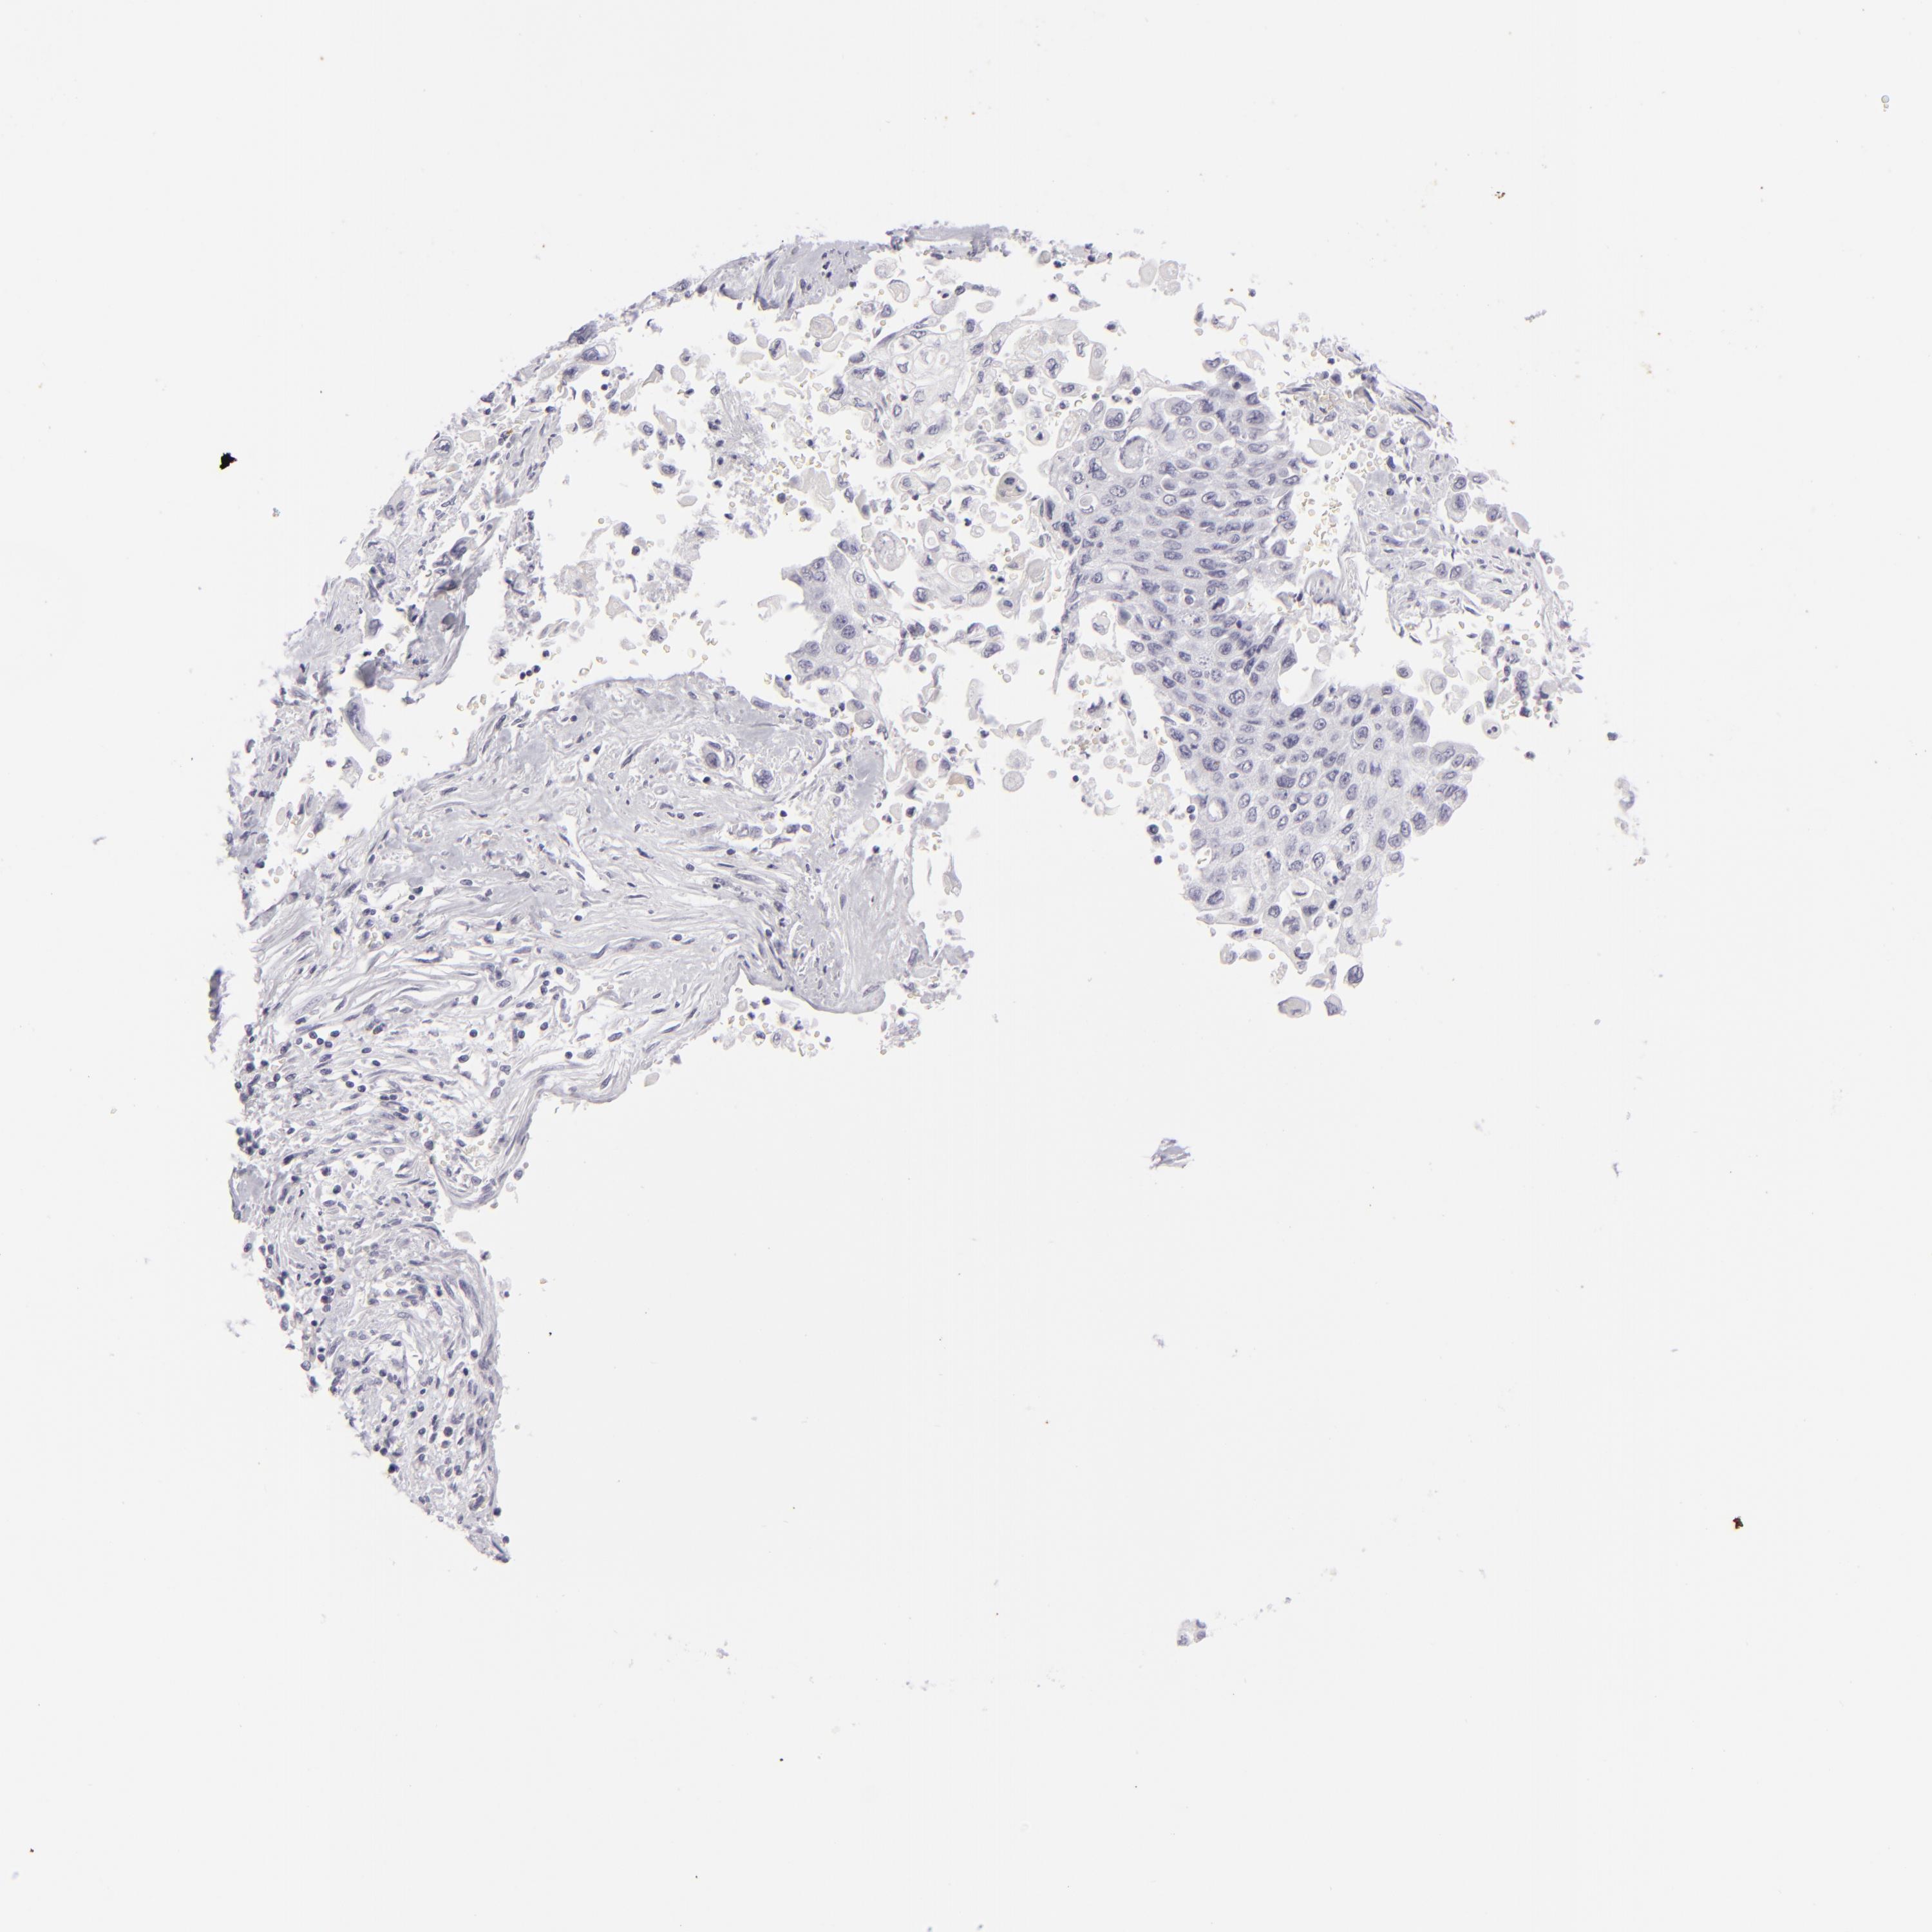

PANCREATIC CANCER - Protein expressioni

A mouse-over function shows sample information and annotation data. Click on an image to view it in a full screen mode. Samples can be filtered based on level of antibody staining by selecting one or several of the following categories: high, medium, low and not detected. The assay and annotation is described here.

Note that samples used for immunohistochemistry by the Human Protein Atlas do not correspond to samples in the TCGA dataset.

Antibody stainingi

Antibody staining in the annotated cell types in the current human tissue is reported as not detected, low, medium, or high, based on conventional immunohistochemistry profiling in selected tissues. This score is based on the combination of the staining intensity and fraction of stained cells.

Each image is clickable and will lead to virtual microscopy that enables deeper exploration of all samples and also displays staining intensity scores, fraction scores and subcellular localization as well as patient and tissue information for each sample.

Antibody HPA017917

Antibody HPA062908

Antibody CAB002153

Adenocarcinoma, NOS